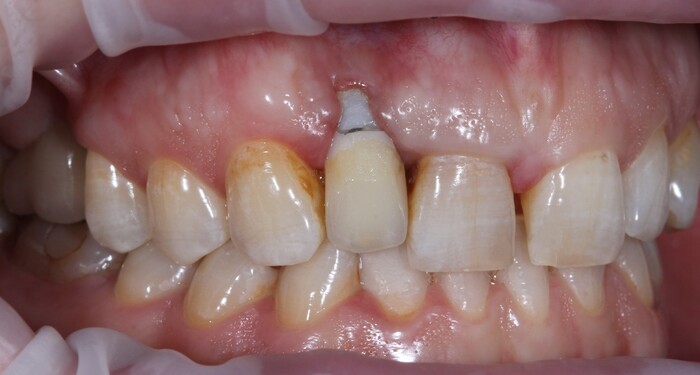

Но мне повезло, ко мне на прием пришла прекрасная девушка (а не усатый господин в плаще на голое тело) с ужасной, с ее слов, проблемой. Когда-то давно ей поставили имплантат в области верхнего бокового резца, но в связи с тем, что положение имплантата было неправильным, а одномоментно с имплантацией пластики десны не проводилось, последняя начала постепенно «подниматься», оголился абатмент (та часть, «за которую держится коронка»). Со слов пациентки, тем же доктором была предпринята попытка сделать пластику десны, не снимая этой коронки. Но, увы, развился некроз, что только усугубило ситуацию.

На момент моего осмотра это выглядело так:

Согласитесь, не особо эстетично. Ортопантомограмма: